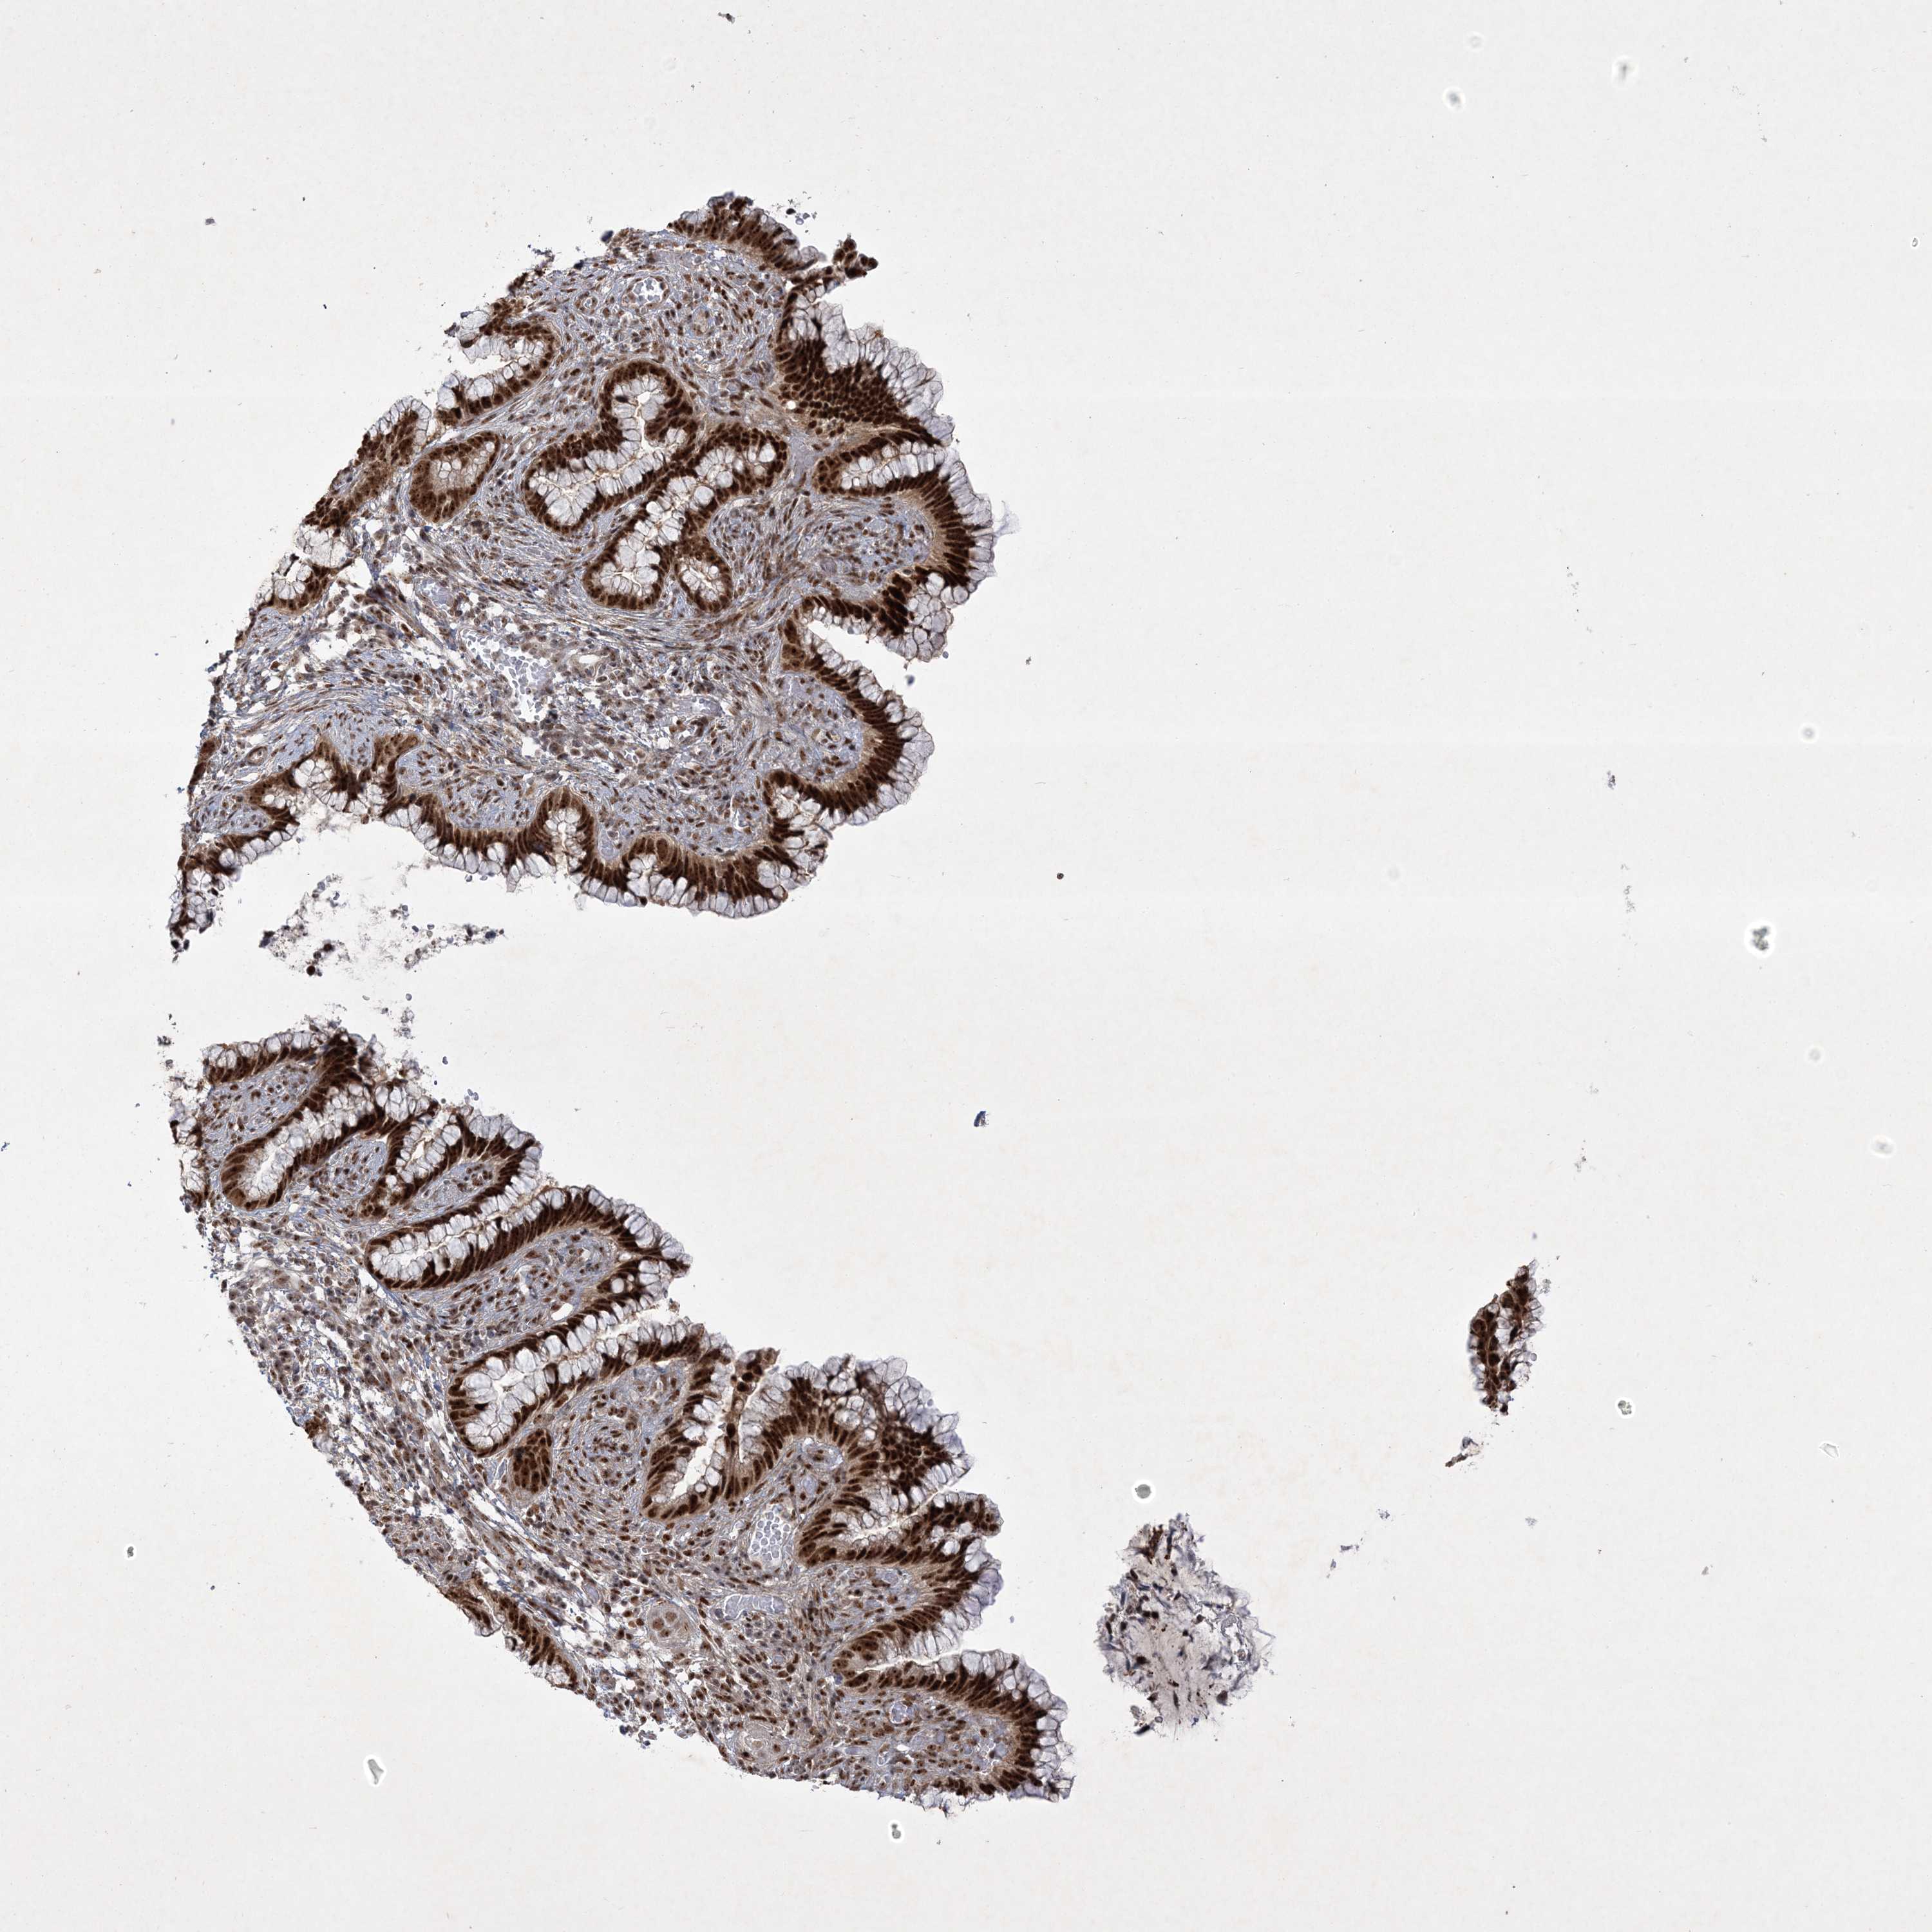

CERVICAL CANCER - Protein expressioni

A mouse-over function shows sample information and annotation data. Click on an image to view it in a full screen mode. Samples can be filtered based on level of antibody staining by selecting one or several of the following categories: high, medium, low and not detected. The assay and annotation is described here.

Note that samples used for immunohistochemistry by the Human Protein Atlas do not correspond to samples in the TCGA dataset.

Antibody stainingi

Antibody staining in the annotated cell types in the current human tissue is reported as not detected, low, medium, or high, based on conventional immunohistochemistry profiling in selected tissues. This score is based on the combination of the staining intensity and fraction of stained cells.

Each image is clickable and will lead to virtual microscopy that enables deeper exploration of all samples and also displays staining intensity scores, fraction scores and subcellular localization as well as patient and tissue information for each sample.

Antibody HPA036295

Antibody HPA036296

Staining

High

Medium

Low

Not detected

Intensity

Strong

Moderate

Weak

Negative

Quantity

>75%

75%-25%

<25%

None

Location

Nuclear

Cytoplasmic/membranous

Cytoplasmic/membranous,nuclear

Squamous cell carcinoma, NOS

Adenocarcinoma, NOS